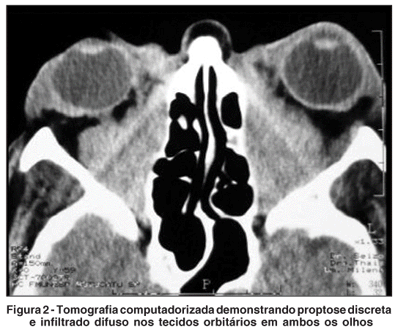

Na tomografia computadorizada de órbita observou-se infiltração difusa dos tecidos orbitários bilateralmente, principalmente na região retro-ocular, sem contornos definidos, associada à proptose axial (Figuras 2 e 3).

A tomografia computadorizada de órbita revelou infiltração difusa dos tecidos orbitários, aspecto que fala a favor de linfoma. Apesar da tomografia auxiliar no diagnóstico, o exame histológico é o que define o quadro, tendo a biópsia da gordura orbitária revelado LL//LLC, mais especificamente um subtipo que constitui o grupo de baixo grau (classificação Working formulation)(7,9), posteriormente também detectado pela biópsia da medula óssea.